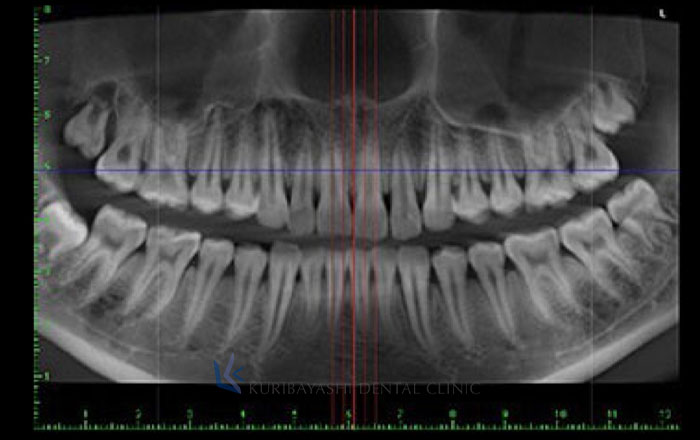

CTを使うことで、顎の部分を3次元の立体画像で撮影することができるため、より精度の高い審査・診断が可能になります。

そこで、X線の装置(CTなど)を使い、歯や骨の中を擬似的に輪切りにして、内側も見ることで、人体に物理的に傷をつけずに情報を得ることができます。

歯周病に関しては、歯周病によって、歯を支える骨がどれだけ溶けてしまっているかが分かります。

どの位置に、どのくらい骨の量が足りなくなっているかで、次の処置の判断がしやすくなります。

親知らず抜歯など、抜歯処置を行う場合にCT撮影を行うことで、歯の根っこと神経の近さを知ることができます。

抜歯時に、顎の中にある太い神経(下顎神経)と言われる部分を傷つけてしまうと、麻痺などの後遺症が出てしまう場合があるので、事前に検査が必要ですが、CT撮影ではそれを知ることができます。

また、インプラント治療を行う場合は、歯と歯の位置、骨の厚さや幅を考慮してインプラントを埋め込む場所を探します。そ

の場合、CT撮影を行うことで、どこにインプラントすれば、より良いか、を判断することができます。